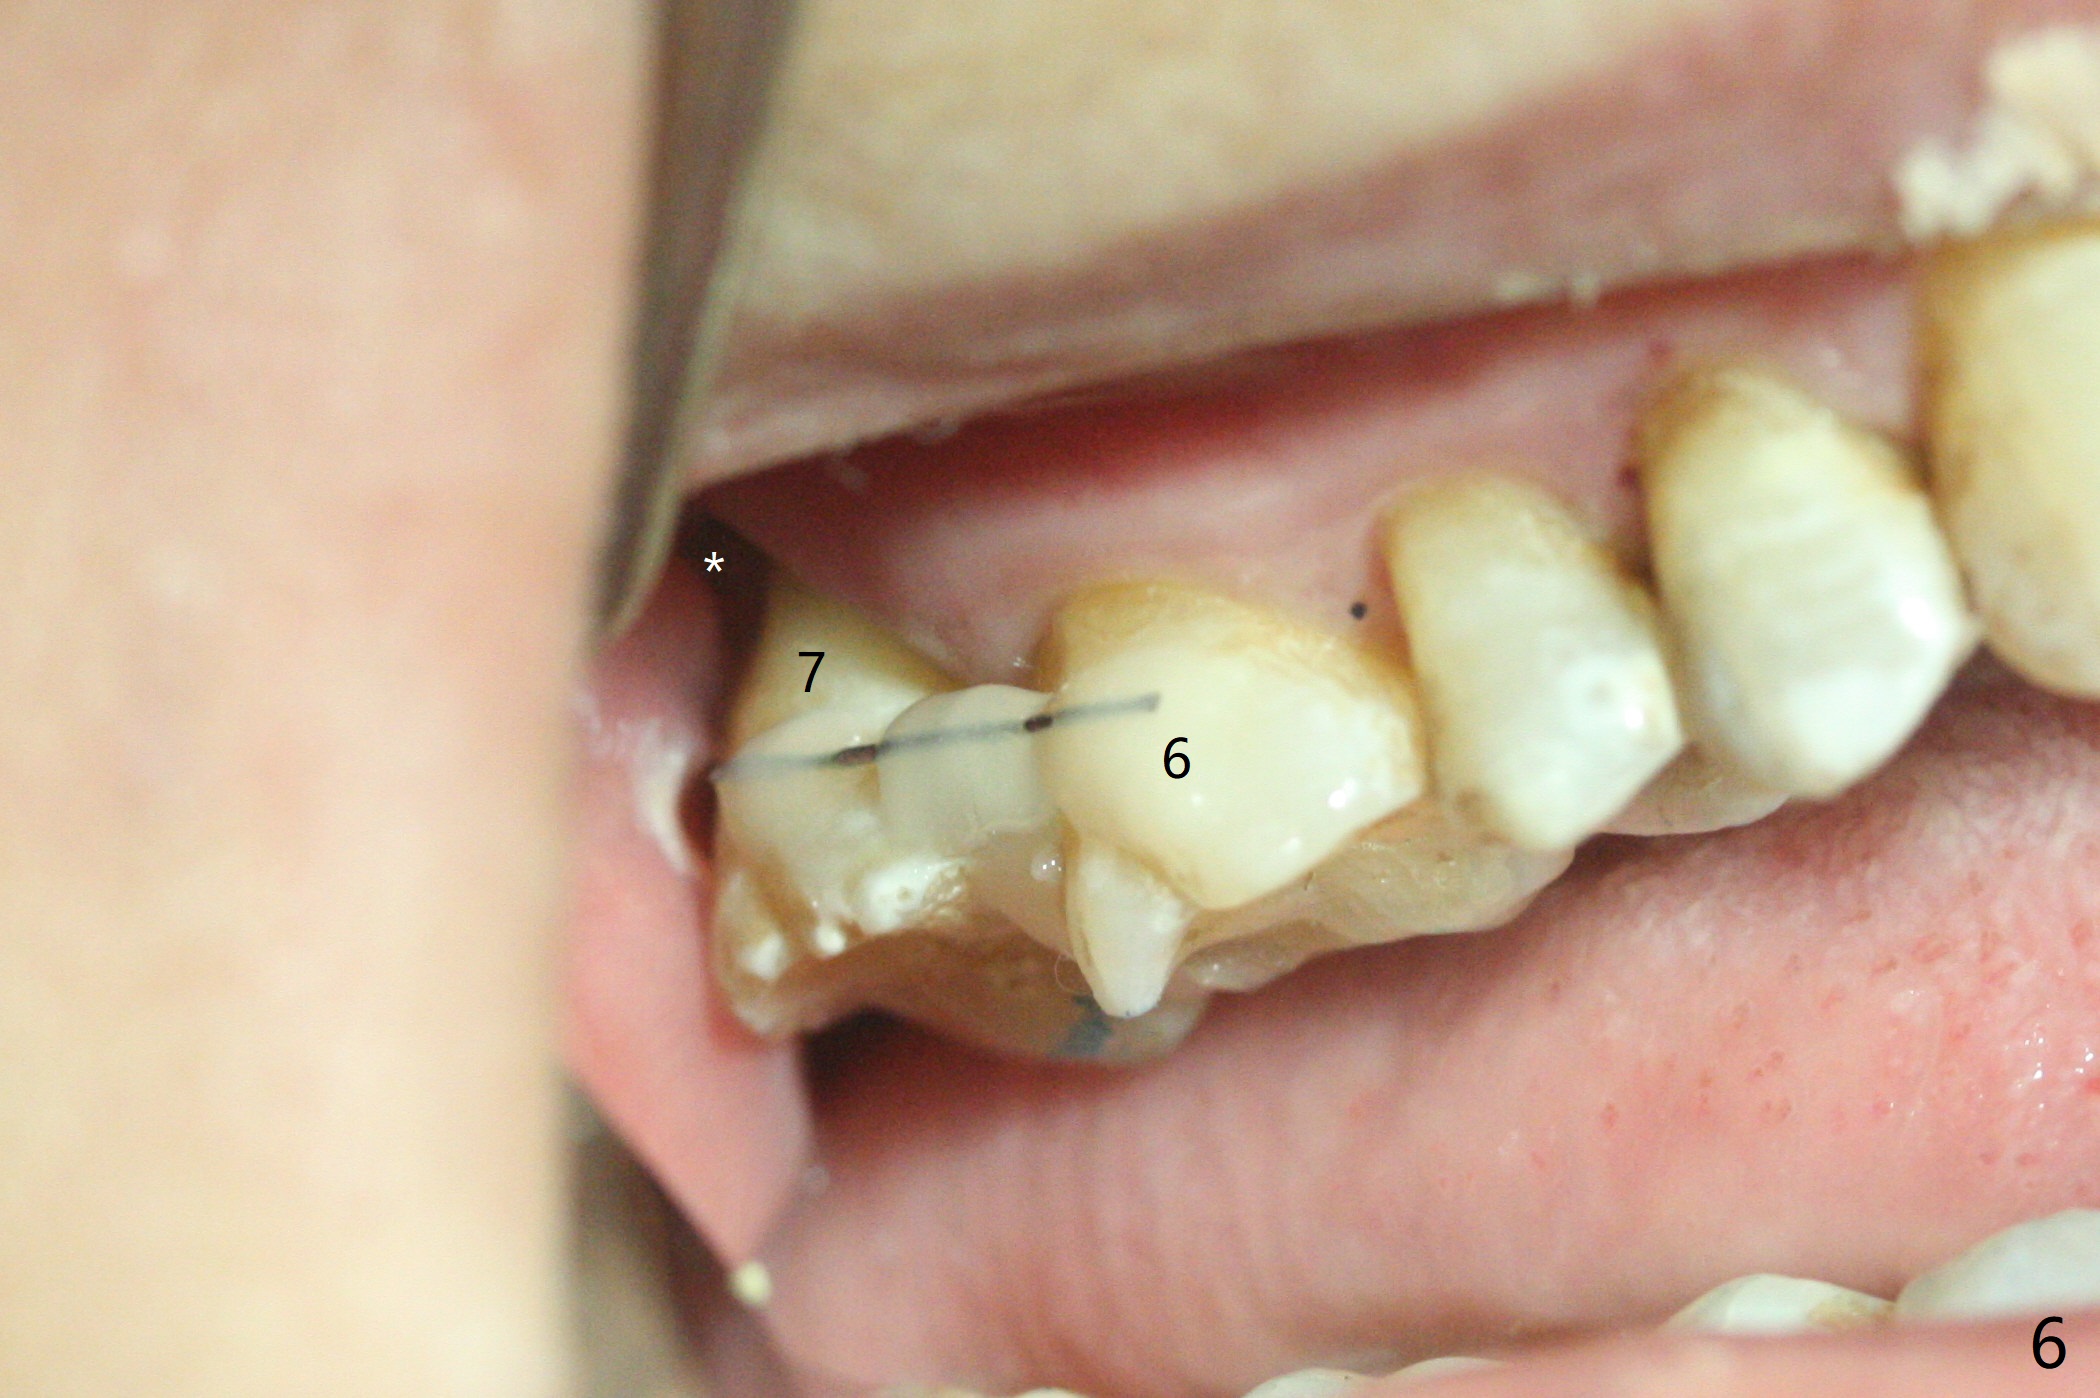

59岁女两年前就诊,主诉右上7,8之间食物坎塞,没有注意7骨质吸收(图一),以为是8过度延申所致拔除,而且远中颊侧,腭侧根断裂(间接说明咬合力大),前者拔除,而后者滞留。如果不拔除,现在支撑导板多好。两年后病人认为断根长出来,其实腭侧根尖仍在骨中(图二(半年前拍摄):箭头),而7骨质吸收更严重,松动2度,怀疑根裂(咬合力大)。同时病人可能有骨质疏松,拔除即刻种植,基台一定要短,一旦牙槽窝愈合,考虑取出临时牙冠,减少微动。取模前,进行渐进性负荷。术前服用Z Pack,准备上颌窦提升,PRFx2。CT显示上颌窦提升不需要,植体可以植入腭侧窝(图三)。 CT冠状切面(图四),矢状切面(图五)显示必须使用长袖的基台(粉红色)固定粘性骨粉(红色),这样植体(绿色)稍微可以种得浅些。箭头:cotton roll(颊侧牙龈沟)。为了让病人在制作导板时舒服些,利用邻牙做冠外固定7松动牙(III)。7颊侧软组织缺失(图六:*)。